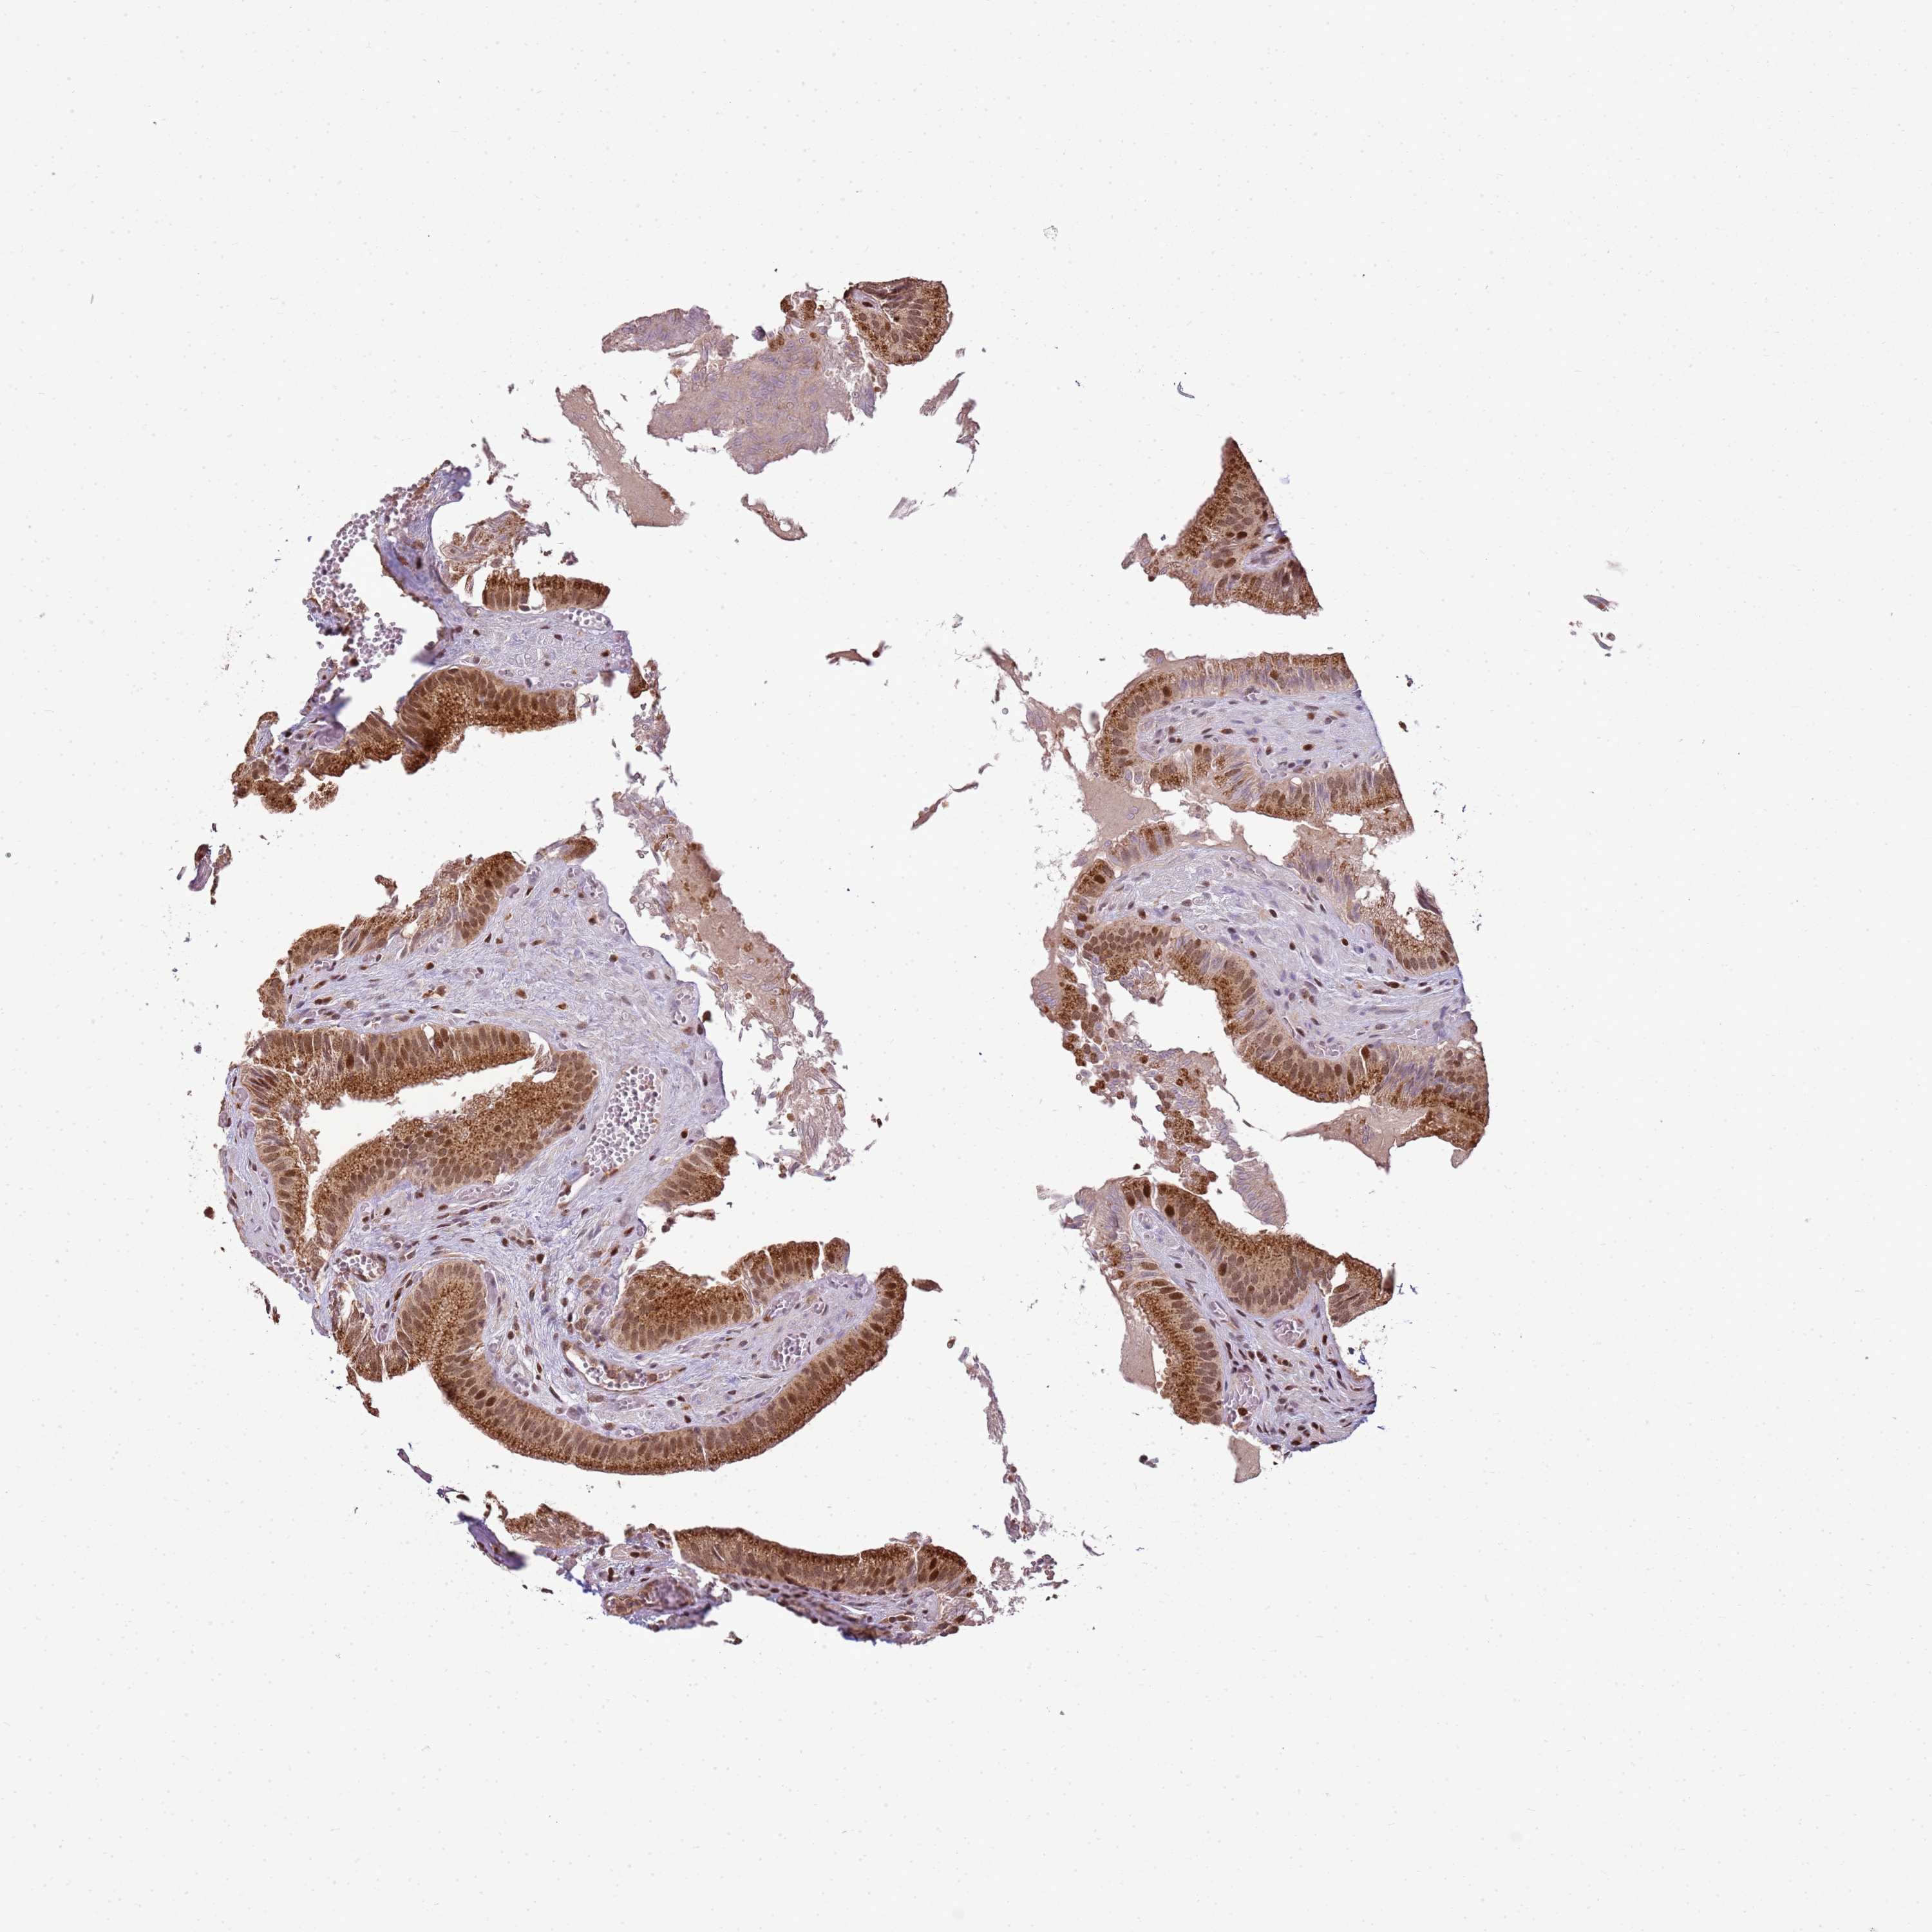

PEX14